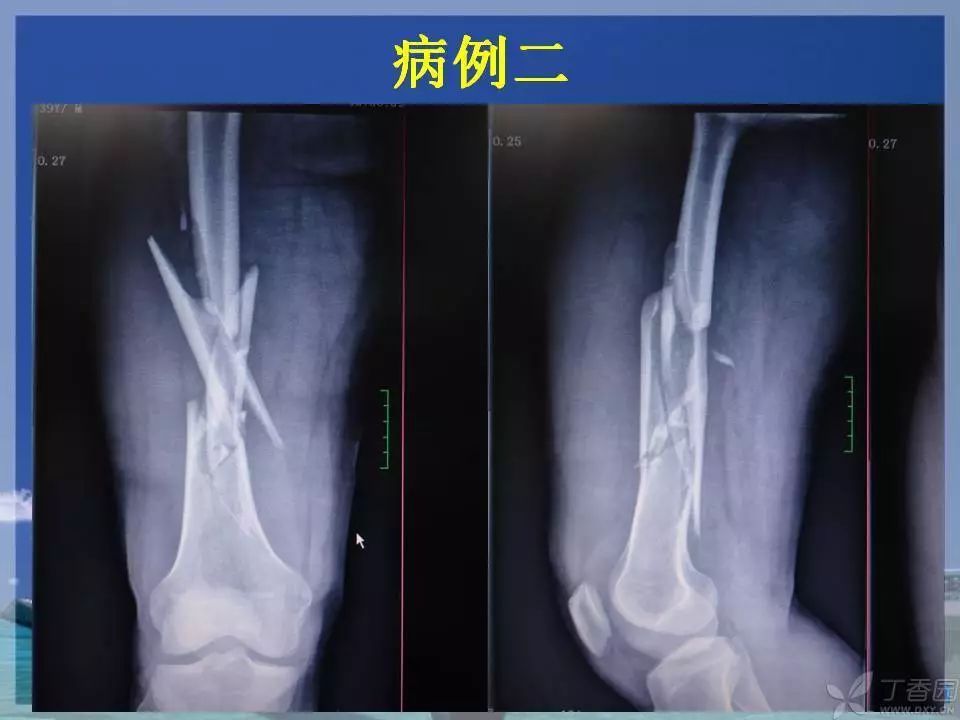

股骨干骨折是临床常见骨折之一,闭合复位髓内针固定治疗已成为首选。那么复位标准是怎样的?骨折块分离多少可以接受?钢丝可不可以用?不扩髓可以吗?相信看完下面这个课件你会有所收获~

1. ppt 中提到蝶形骨块移位大于 1cm 会影响股骨干骨折的愈合,这是一个台湾学者的观点,图中可以看见股骨内侧和后侧已经有骨痂生长,所以说 1cm 这个数据有待商榷。大于 1cm 的移位骨折愈合也不是什么问题。

3. 髓内钉和钢丝不会从内外方向破坏骨的血供。